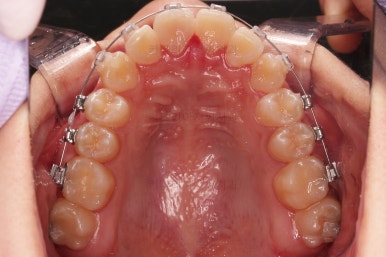

동래교정치과 초진 시의 입 안 모습이에요.

치열이 삐뚤고 덧니가 보이네요.

이번 환자분도 스스로는 보기 싫은 이유가 첫 번째였지만 사진에서도 보시다시피 양치가 잘 안되어 치석도 많고 잇몸도 부어있는 상태였어요.

그리고 앞니들이 마모가 많이 되어 있어서 각각의 치아들이 원래 형태에서 많이 변형된 것을 볼 수 있네요.